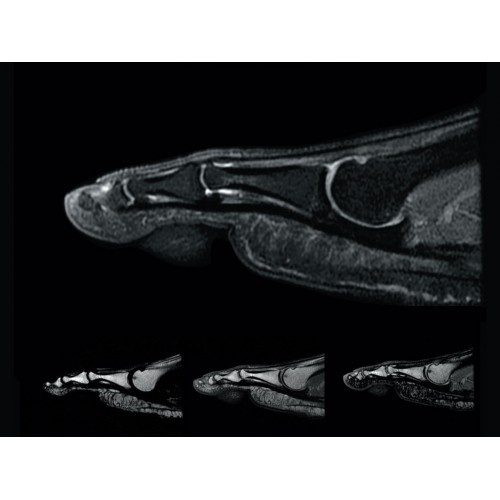

• РЧ-катушки, оптимизированные для исследования конкретных участков тела — элементы катушек высокой плотности располагаются вокруг исследуемых участков тела и при необходимости обеспечивают расширенный охват и оптимальное качество изображений при каждой процедуре.

• Широкое поле зрения — поле зрения шириной 50 см позволяет охватывать крупные анатомические области за меньшее число сканов.

МР-томограф Optima MR450w с диаметром туннеля 70 см обеспечивает более комфортные условия для пациентов, в первую очередь, для полных людей, детей и лиц, страдающих клаустрофобией. При этом повышенное удобство для пациентов обеспечено не только нешироким туннелем — клинические приложения нового поколения сокращают продолжительность исследований, а улучшенный поток воздуха обеспечивает удобный микроклимат во время исследования.